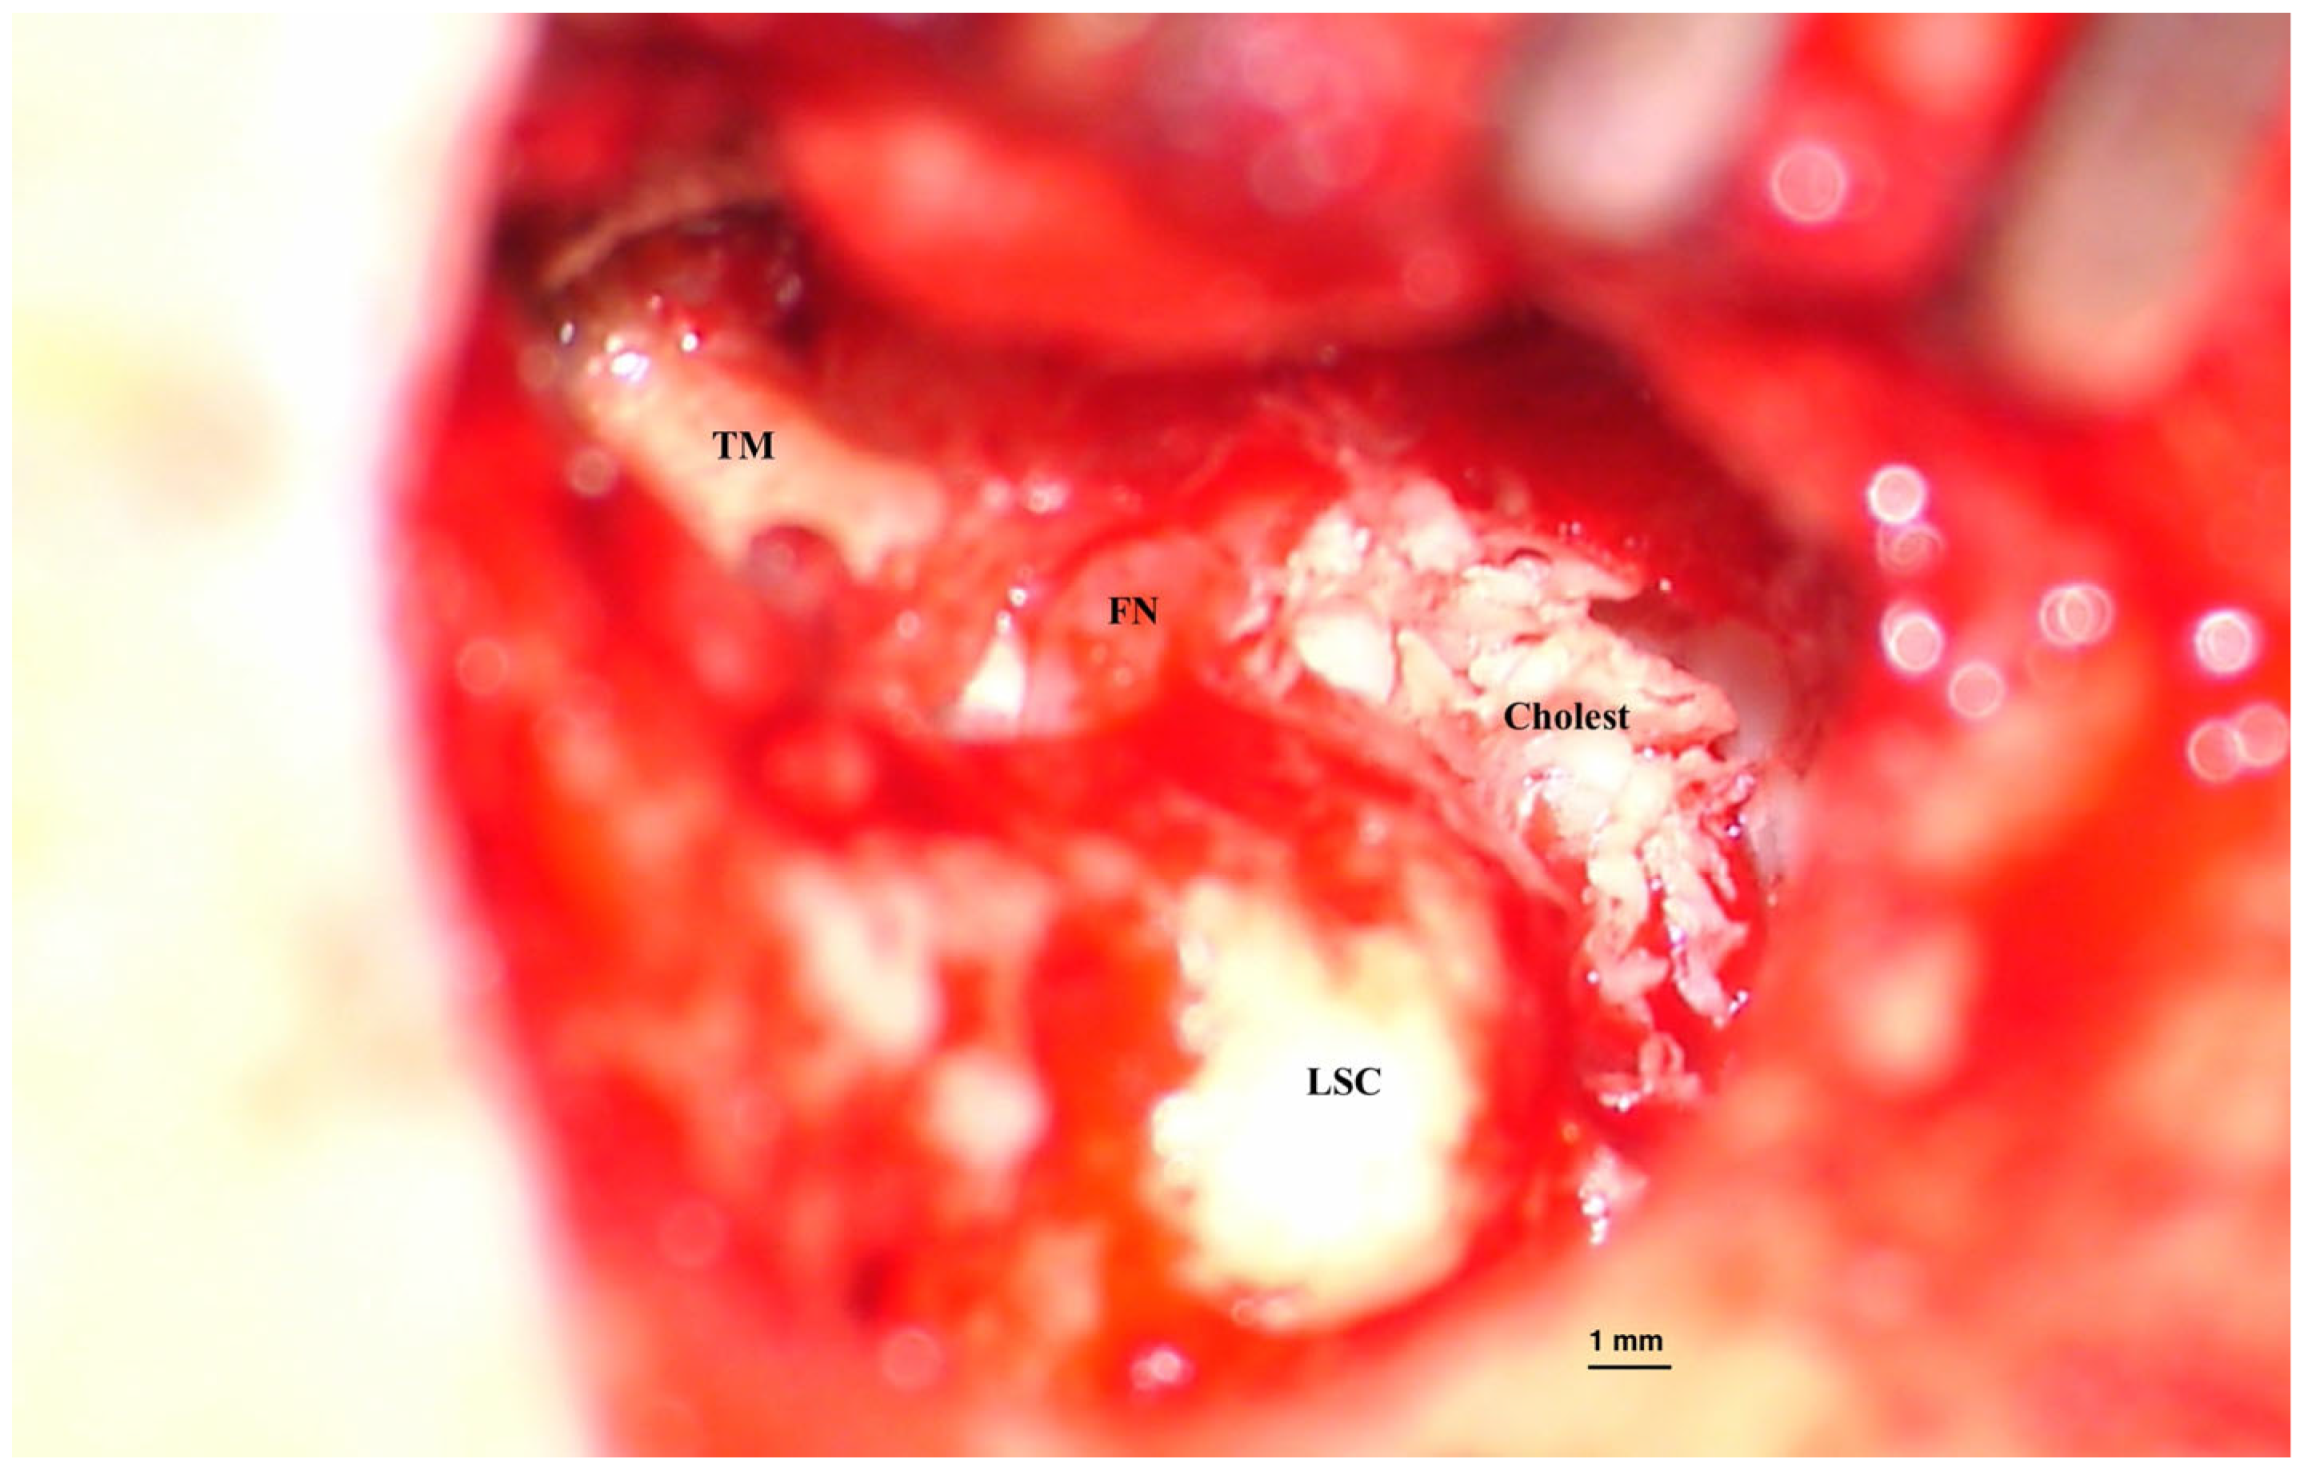

• Primary acquired, developed from a retraction pocket, due to Eustachian tube dysfunction or chronic otitis media (Figure 2);

Figure 3. Recurrence of cholesteatoma in an open mastoid cavity. Postoperative imaging of an open mastoidectomy cavity after cholesteatoma surgery. The lining of the cavity is healed but at a certain location we notice a cholesteatoma recurrence (pearl-like) (blue arrows) developing and covered by a normal epithelium. Left untreated, it will create bone erosion underneath and enlarge, destructing the remaining of the temporal bone. Picture taken with Zeiss TIVATO 700 microscope (ZEISS Microscopy, Jena, Germany). (from D.C.G’s. personal collection).